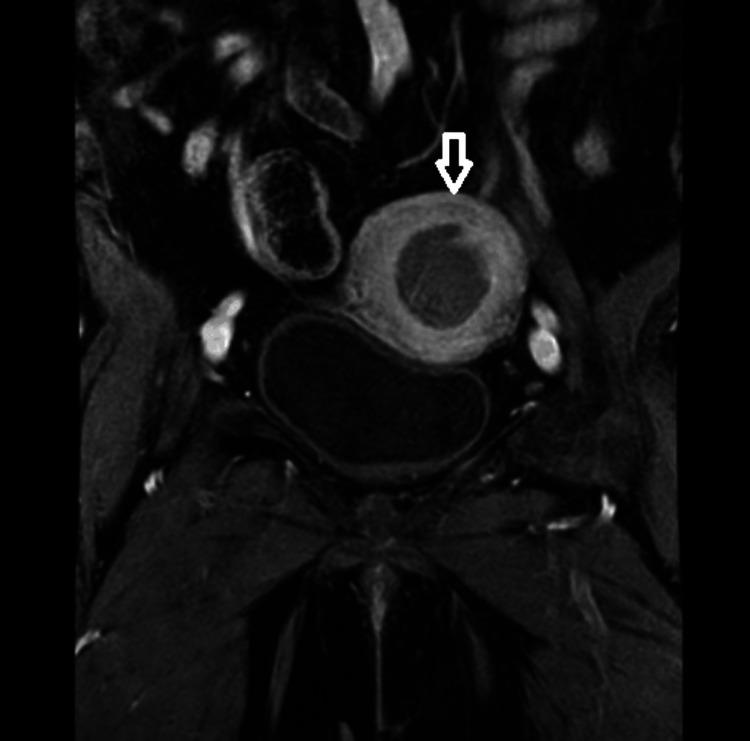

The case report details the adaptive radiotherapy management of a 75-year-old female diagnosed with high-grade endometrial carcinoma. The patient, who was known to be hypertensive with no other comorbidities and no family history of cancer, presented with a complaint of bleeding per vagina for six months. Following extensive investigations, she underwent a laparoscopic radical hysterectomy. Postoperative histopathology confirmed endometrial adenocarcinoma International Federation of Gynecology and Obstetrics (FIGO) stage IA, grade III. The adjuvant treatment plan included adjuvant chemoradiotherapy to the postoperative tumor bed and draining lymph nodes. On planning computed tomography (CT), the patient's lymphocele responded remarkably to radiation therapy, an unusual outcome that underscores the potential efficacy of adaptive radiotherapy in complex cases.

摘要

该病例报告详细介绍了一名75岁女性高级别子宫内膜癌的自适应放射治疗管理情况。该患者已知患有高血压,无其他合并症,且无癌症家族史,因阴道出血六个月前来就诊。经过广泛检查后,她接受了腹腔镜根治性子宫切除术。术后组织病理学证实为国际妇产科联盟(FIGO)IA期、III级子宫内膜腺癌。辅助治疗方案包括对术后肿瘤床和引流淋巴结进行辅助放化疗。在计划计算机断层扫描(CT)时,患者的淋巴囊肿对放射治疗反应显著,这一不寻常的结果突出了自适应放射治疗在复杂病例中的潜在疗效。